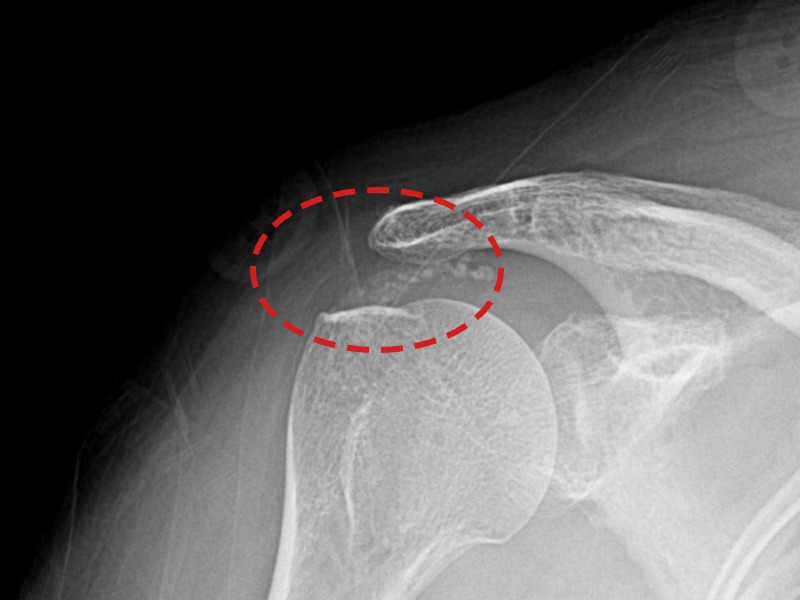

[촬영시기:21.11.04~21.11.09]

[석회분쇄흡입술] 우측 어깨 극심한 야간 통증으로 수면이 불가능해진 50대 여성 환자로, X-ray에서 우측 극상근건 내 석회 침착이 확인되어 석회분쇄흡입술을 시행하였습니다.